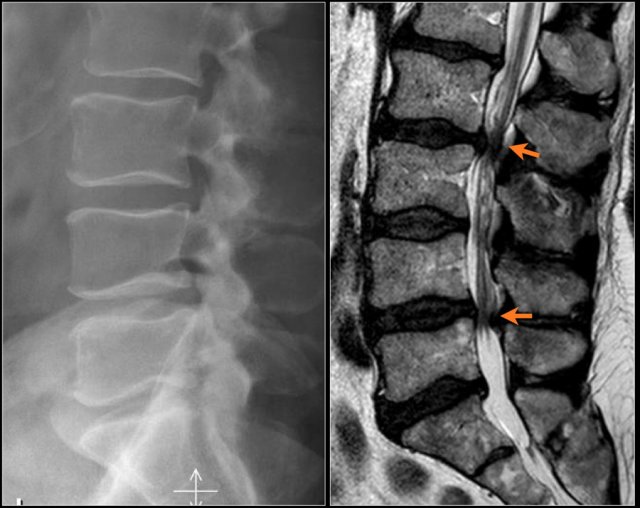

B. Badania Obrazowe: Rentgen, MRI, Tomografia Komputerowa

- Rentgen: Rentgen kręgosłupa może pomóc lekarzowi w wykryciu ewentualnych zmian degeneracyjnych, złamań, zwyrodnień stawów czy przemieszczeń kręgów. Jest to często stosowane badanie obrazowe wykonywane w pierwszej kolejności.

- MRI (Obrazowanie metodą rezonansu magnetycznego): MRI kręgosłupa umożliwia uzyskanie bardziej szczegółowych obrazów struktur miękkich, takich jak dyski międzykręgowe, więzadła czy rdzeń kręgowy. Jest to pomocne badanie w przypadku podejrzenia uszkodzenia tkanek miękkich czy ucisku na struktury nerwowe.

- Tomografia Komputerowa: CT kręgosłupa może być pomocna w ocenie kości kręgosłupa, zwłaszcza w przypadku urazów, złamań czy oceny stanu stawów.